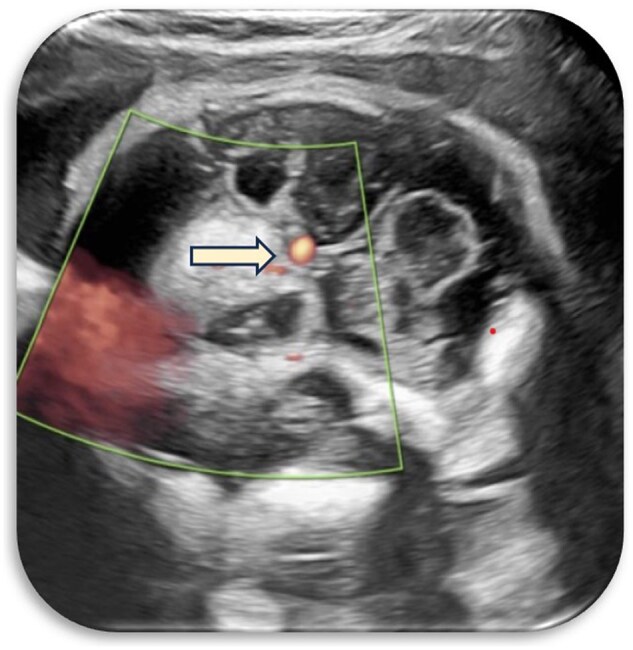

Unravelling fetal enigmas: a case of suprasellar lesion.